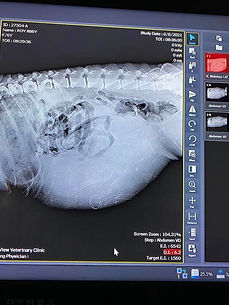

Abby had an X-ray done this morning (6/8/21) which showed 6 skull caps but 7 spines. She is a little girl and so full that it is felt she will not go to due date of June 22 but the weekend before. Check back for updates on the birth.